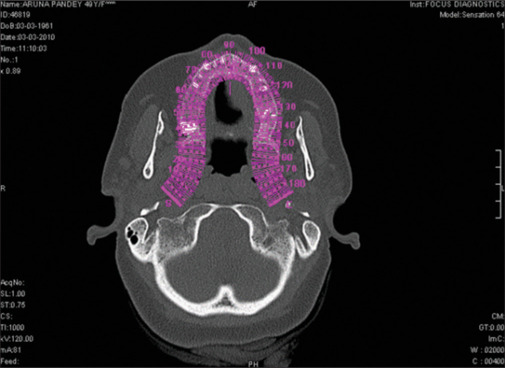

Purpose: The purpose of this study was to examine the relationship between the local bone density derived from a cone-beam computed tomography (CBCT) scan from different sites in the maxilla and mandible and the insertion torque values, for the success of oral implants.

Materials and methods: A total of 73 patients who reported to our unit, with missing teeth and a desire for replacement with dental implants, were included in this study. A total of 118 implants were placed from 2008 to 2011. The number of male and female patients included in the study was 43 and 30, respectively. The mean age of the patients was 43.2 years. NobelReplace Select Tapered Implant system was used for all patients.

Results: The mean bone density of all 118 implants was 620 ± 251 Hounsfield units (HU). The mean bone density and insertion torque values of the six failed implants were 459 ± 131 HU and 28 ± 5 Ncm, respectively. The mean bone density and insertion torque values of the 112 successful implants were 678 ± 217 HU and 36 ± 2 Ncm, respectively. A significant strong positive correlation was observed between bone density and torque at all sites.

Conclusion: CBCT is a useful tool to determine the bone density of the concerned areas before implant placement. The valuable information derived from the CBCT about bone quality may help clinicians to avoid the placement of implants into the very poorest qualities of bone, where failure is more likely.